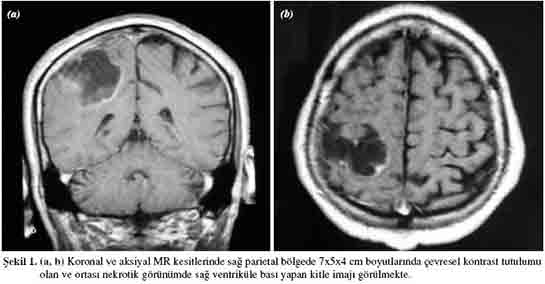

Tanı Yöntemleri Beyin metastazının tanısı, genellikle görüntüleme yöntemleri ile konulmaktadır. Bu yöntemler arasında:

Bu görüntüleme yöntemleri, beyin dokusundaki anormalliklerin belirlenmesi ve metastatik lezyonların sayısının ve boyutunun değerlendirilmesi açısından büyük önem taşımaktadır. Tedavi Seçenekleri Beyin metastazı tedavisi, hastanın genel sağlık durumu, metastazın sayısı ve konumu gibi birçok faktöre bağlı olarak değişiklik göstermektedir. Genel tedavi yöntemleri arasında: